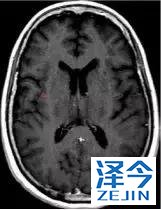

一位77岁的女性患有EPS15-NTRK1 IV期非小细胞肺癌,我们可以看到她的双肺满是病灶,并且出现了肝脏和脑转移,可以说是非常非常晚期了,

脑转移病变显示缩小了95%!

初始, 2018年6月 3周期 2018年8月